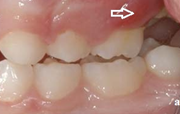

Ülemise hambakaare kitsenemine ehk tagumiste hammaste risthambumus.

alumine hambakaar on laiem ülemisest

ülemine hambakaar on alumisest laiem nõnda palju, et hambad kokku ei puutu